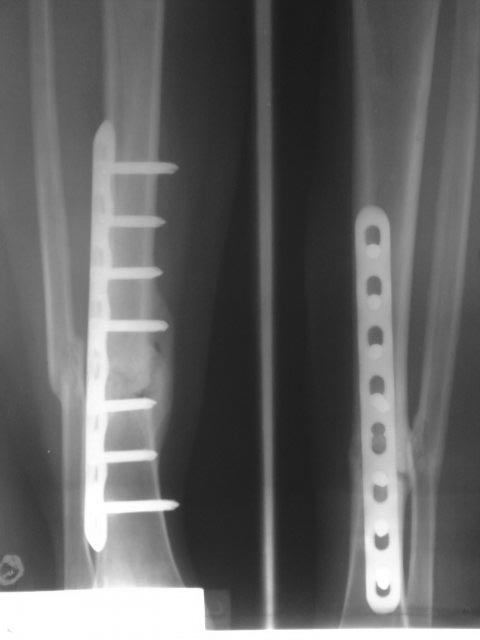

Здравствуйте! Спасибо за предоставленные снимки! Если судить по снимкам, то перелом сросся (костная мозоль со всех сторон). Необходима трансформация (уплотнение) костной мозоли, а для этого нужны нагрузка и время. Удаление пластины освободит наружный кортикал и распределит нагрузку равномерно по всей окружности кости. Что касается аутопластики, то она не показана при гипертрофическом псевдоартрозе. Ещё раз спасибо!

По данным рентгенограммам - перелом сростается. Исключить сомнения - сделать МСКТ. Если на МСКТ - данных за ложный сустав нет, то удалить металлоконструкцию и пользоваться ортезом на голень до достижения более прочной костной мозоли по данным контрольных R-грамм.

Еще бы понятно околосуставной, но зачем диафизарный перелом tibia в наши дни синтезировать пластиной?

Периостальная спайка вроде там все-таки есть. Наверно, ничего не надо делать. Или далить ближайшие к перелому винты, чтобы не было концентрации напряжений.

Доброго дня, Олег... Случай интересный. Непонятно расположение пластины( наружная установка имеет конкретные узкие показания) и выбор и количество винтов. В тактике, скорее соглашусь с доктором Челноковым, но если не уберете ближайшие к зоне перелома блокированные винты, скорее всего произойдет перелом конструкции. Уберите, может перелом срастется в условиях относительной стабильности. А пластика в этом случае, конечно не показана...